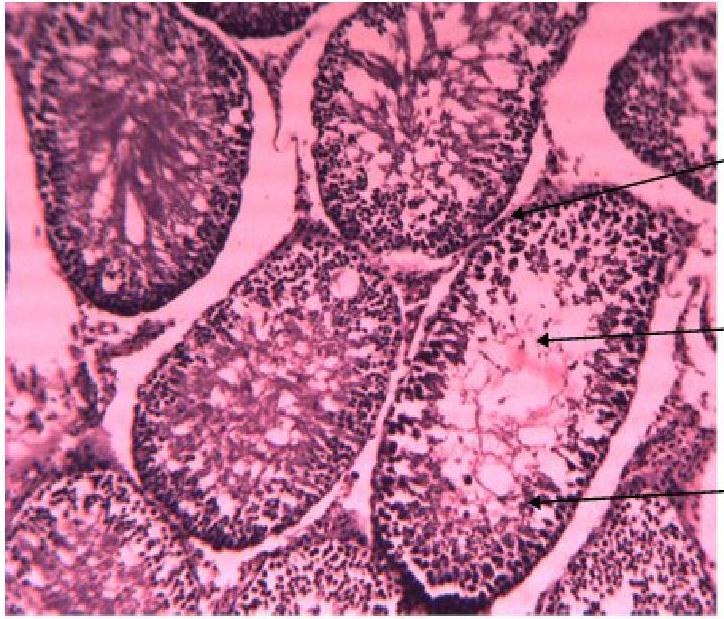

Pharmacology

Alhaji HM, Abubakar R, Musa ES, Lekko YM, Adam C, Muktar BM, Ngulde SI, Yahi D and Ojo NA